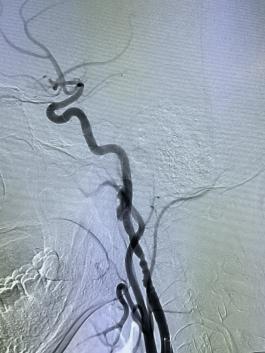

根據(jù)阿杰的病情,醫(yī)生馬上給阿杰實施靜脈溶栓和急診介入取栓手術治療,最終順利取出了堵塞腦血管的血栓,開通了閉塞血管。

左圖:開通后的血管

右圖:取出的血栓

入院2小時后,阿杰就恢復了“自由身”,左半邊身子可以重新活動了。10天后順利康復出院,并且完全可以活動自如了。